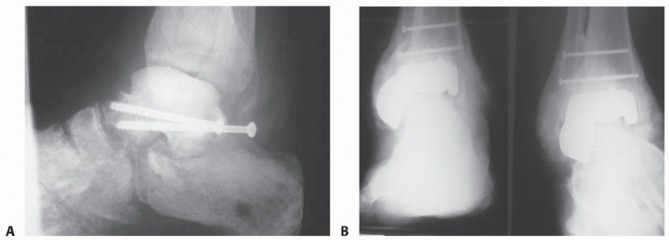

INDICATIONS Talar body avascular necrosis with collapse or infection ( FIG 1A ) is one indication for femoral…